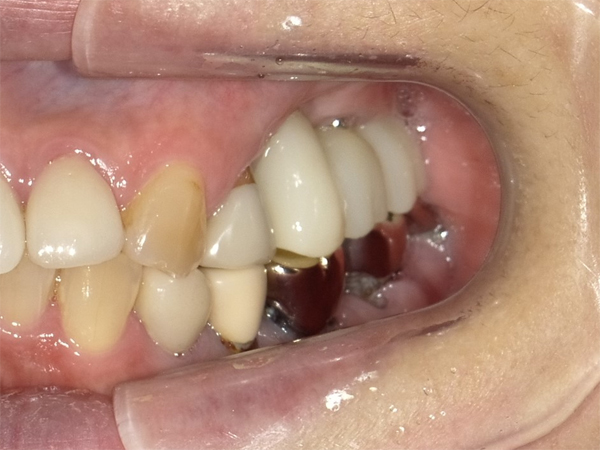

(50歳代 男性)

最終補綴物装着時の口腔内所見

他院では、骨がなく、インプラントはできないといわれたことで患者自体が非常にコンプレックスに近いものを感じておられました。「骨がないからインプラントができない」との一言が、患者さんにとっては自分はほかの人と違って・・・と考えるきっかけにもなる。東洋人は上顎洞が発達していること。サイナスリフト自体も経験豊富な治療医にとっては安全な治療ということを理解していただくことも大切であると思われた。

術後は良く噛めて機能面も十分に回復でき、患者さん自身も非常に喜ばれていました。他の不良補綴物や対側のインプラント治療も今後、行っていきたいとのことで、ともに【よりよい】口腔内を作っていきましょうとお互いにお話しをしています。サイナスリフトは、安易に初心者がチャレンジするものではないことから、そのような症例は専門医に任せることも重要かと思います。